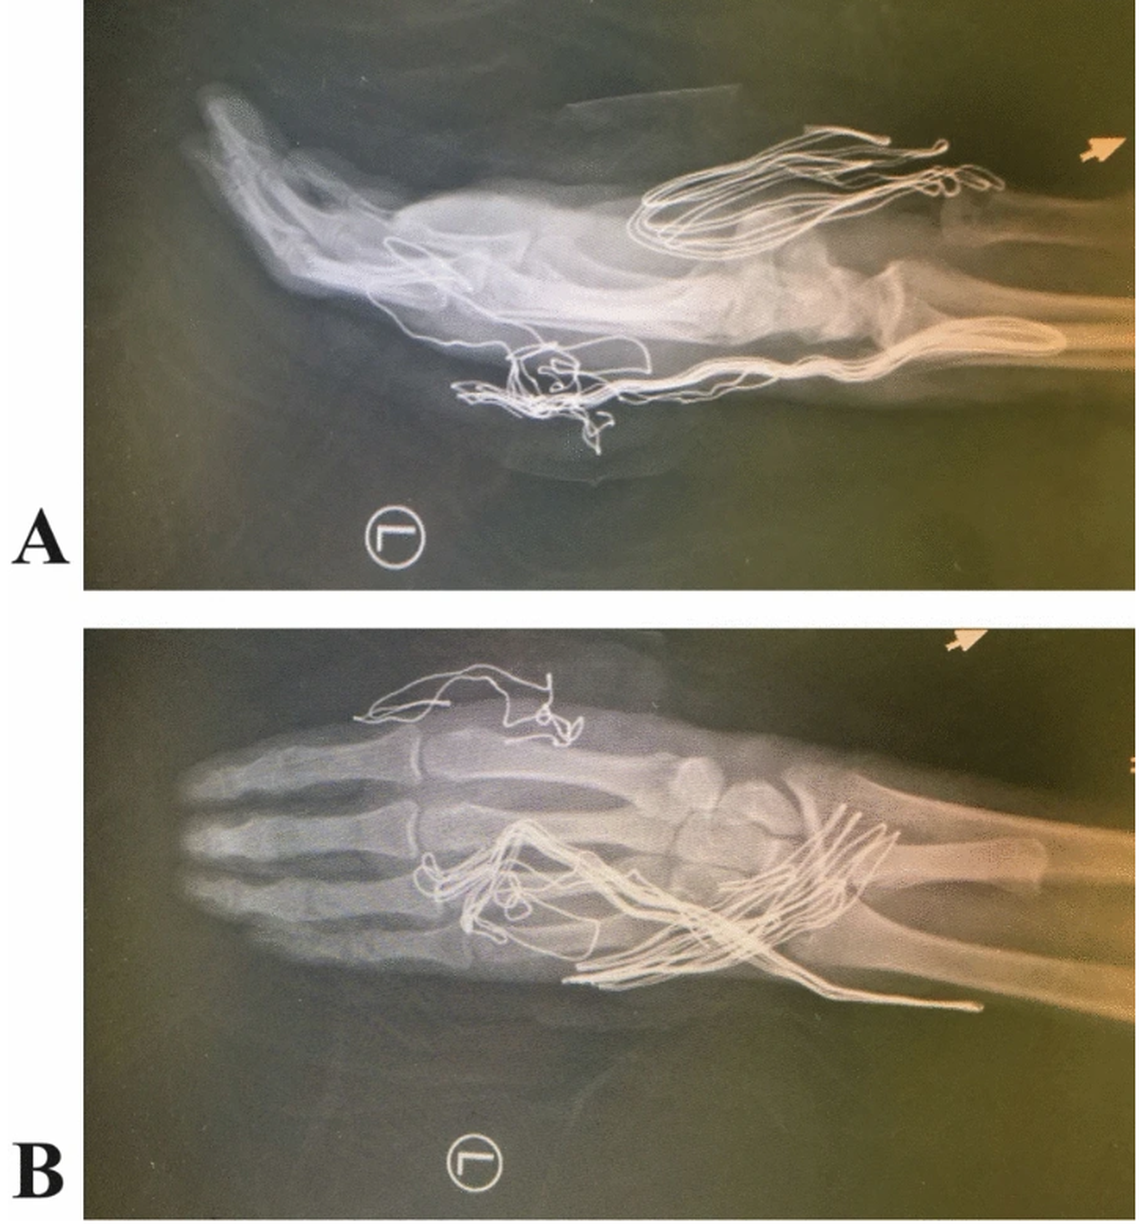

X-rays show the thumb bone embedded on the top of the forearm, appearing in scans as an extra small bone just below the wrist.

The bone of the thumb was “banked” in the man’s arm, appearing on X-rays just below the wrist.

The bone of the thumb was “banked” in the man’s arm, appearing on X-rays just below the wrist. Kafiabadi, et al (2025) Journal of Medical Case Reports